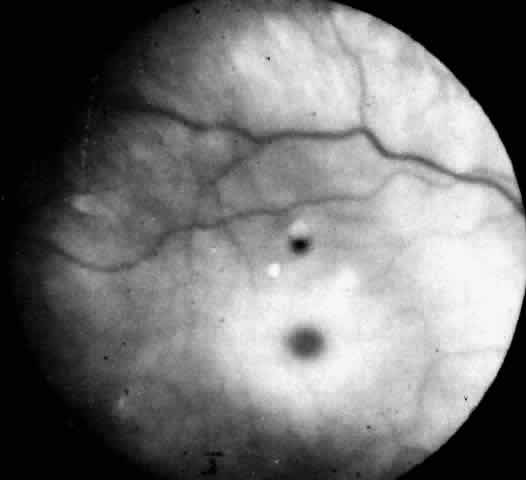

Niemann-Pick disease type A was described by Niemann in 191441 in an 18-month-old Jewish child with hepatosplenomegaly and mental retardation. In 1927, Pick42 described the histopathology characterized by large numbers of vacuolated or “foam” cells in many organs and tissues in the body. Subsequently, Klenk, in 1934,43,44 identified the lipid stored as sphingomyelin. CLINICAL MANIFESTATIONS. Infantile Niemann-Pick disease type A has its onset in early infancy at 6 months of age. The disease is characterized by failure to thrive, a protuberant abdomen due to an enlarging spleen, and severe involvement of the CNS with progressive loss of motor function. Death occurs by the third year of life. Approximately half of these patients are the offspring of Ashkenazi Jews. In Niemann-Pick disease type B, only visceral involvement is noted. Onset is in late childhood between 3 and 11 years of age or in adult life with splenomegaly and pulmonary infiltrates. Intellect is normal. Infants affected with type B are of mixed ethnic background. Niemann-Pick disease type C, the subacute form, presents in infancy with neonatal hepatitis or later in childhood with moderate splenomegaly and gradual neurologic deterioration. Many patients have seizures and limitation of vertical gaze. The presence of down-gaze paresis is the most typical defect. Sea-blue histiocytes in the bone marrow are common. These patients usually die before the end of their second decade. Niemann-Pick disease type D is clinically similar to type C. This designation is limited to an inbred group of cases traced to a couple who lived in Yarmouth County in Nova Scotia in the late 1600s.45 These patients store sphingomyelin in the tissues in variable amounts. They present with hepatosplenomegaly at 4 to 6 years of age and follow a protracted course. Involvement of the CNS occurs late. Many patients become ataxic and develop seizures. The type E phenotype is characterized by adult onset, mild splenomegaly, foam cells in the bone marrow, and the absence of neurologic signs. OCULAR MANIFESTATIONS. Niemann-Pick Disease Type A. A cherry-red spot of the macula is present in 50% of cases.46 Cogan47 noted no distinction between the appearance of the cherry-red spot in infantile Niemann-Pick disease and that seen in Tay-Sachs disease. Others have reported subtle differences in the color of the fovea and/or the halo and in the degree of opacification of the peripheral retina.48–51 All infants with Niemann-Pick type A disease become blind late in the course of the illness, and optic atrophy develops. Walton and associates51 also noted subtle lens opacities and peculiar corneal clouding, suggesting widespread ocular involvement in this disorder of sphingolipid metabolism. Niemann-Pick Disease Type B. A unique retinal abnormality, the macular halo syndrome has been reported in seven cases of Niemann-Pick disease type B, three enzymatically proven52–54 and four prior to enzyme verification described between 1950 and 1970.55–58 Symmetrical punctate crystalloid ring-form opacities about the foveas were observed in each case with no visual impairment. Cogan and Federman56 in one of the early cases were the first to publish a fundus photograph of the macular halo (Fig. 6). The patient was a 24-year-old woman with hepatomegaly, no neurologic signs, and a reticuloendotheliosis of unclassified type. Both fundi showed doughnut-shaped opacities about the foveas. The opacities were described as yellowish white scintillating granules forming a relatively sharp border on the inner edge of the ring and a ragged border on the outer edge of the ring. Despite this condition the patient had normal visual acuity (20/15 [6/5]) and no scotoma. The first case verified enzymatically was reported by Harzer and associates in 1973.52 The assay showed a sphingomyelinase level in leukocytes that was less than 10% of normal. Although these scattered reports were in the literature, it was Cogan who clearly identified the lesion and made the association with Niemann-Pick disease type B. Cogan and co-workers53 reexamined their initial patient and added a 21-year-old man with a history of splenomegaly and hyperlipidemia. The diagnosis of Niemann-Pick type B disease in each of these patients was confirmed by finding significantly lower sphingomyelinase levels in cultured skin fibroblasts. They named the condition macular halo syndrome. In these cases, the opacities in the retina formed a halo approximately one-half disc diameter at their outer edge. The halo had a crystalloid appearance. By stereo-ophthalmoscopy, slit lamp biomicroscopy, and fluoroangiography the opacities appeared to occupy various depths of the retina but were most numerous in Henle's fiber layer, causing only minor obscuration of the overlying vessels. The foveal lesion in Matthews and associates' patient54 is similar in size and appearance to the fundus photograph published by Cogan and coworkers. On the basis of stereo biomicroscopy and contact lens examination, Matthews and associates located the lesion in the ganglion cell layer of the retina. The masking effect that the ring lesion had on the perifoveal vasculature in the early fluorescence angiogram was taken as confirmation that the accumulated material is in this superficial layer of the retina. As a result, Matthews and associates proposed that the macular halo represents the smallest or mildest form of a cherry-red spot—findings in conflict with those of Cogan. The precise location of the opacities in the retina remains uncertain, however, because of the lack of histopathology. The available clinical data suggest that such opacities are permanent. For example, the appearance of the macular halo remained unchanged for 15 months in one case,57 4 years in another,52 and more than 20 years in one of Cogan's cases.53 Cogan concluded that the remarkable preservation of normal visual function in all of the cases either was due to hiatuses in the opacities or, less likely, to a localization of the opacities behind the photoreceptors. Niemann-Pick Disease Type C, In Niemann-Pick disease type C neither the macular cherry-red spot nor the macular halo syndrome has been observed. However, differentiating Neimann-Pick disease type C from the other types of Niemann-Pick disease is a clinical syndrome that has been referred to in the literature as ophthalmologic neurovisceral lipidosis,59 vertical supranuclear ophthalmoplegia lipidosis,60–63 and Neville's disease.64 Cogan and co-workers65 have added nine cases to the 30 patients already reported Under these various headings and have recommended an acronym, the DAF syndrome, to denote the three essential features: downgaze paralysis, ataxia/ athetosis, and foam cells in the spleen, liver, and bone marrow. Characteristic of the Niemann-Pick disease type C DAF syndrome is an onset in the first 2 decades of life. There is a characteristic progression of the down gaze paralysis to involve upgaze and eventually horizontal gaze and a total supranuclear ophthalmoplegia. Athetosis and spasticity develop in addition to ataxia. There is extensive infiltration of bone marrow, spleen, liver, and other tissues with foam cells and a variable degree of intellectual impairment. Sphingomyelinase activity in leukocytes and cultured fibroblasts is decreased or normal. The underlying metabolic block is reported to be in the esterification of cholesterol within the cells. Niemann-Pick Disease Types D and E. Niemann-Pick type D disease has no ocular manifestations. Patients with the type E variant may have macular cherry-red spots. NEUROPATHOLOGY. In Niemann-Pick disease sphingomyelin accumulates in excess in the brain and autonomic ganglia. The neurons appear swollen with pale cytoplasm. Ultrastructurally the cells contain concentric lamellated bodies representing storage cytosomes. Inclusion profiles in the viscera, lymph nodes, and foam cells also correlate with an increase in sphingomyelin content. In the eye in Niemann-Pick disease type A with macular cherry-red spots, stored lipid is localized to the ganglion and amacrine cells of the retina most obviously in the parafoveal region. The ganglion cells of the other nuclear layers are unaffected.66 Larsen and Ehlers67 report, however, that the affected ganglion cells are not ballooned, degenerated, or reduced in number. This may account for the retention of vision in their patient and in similar nonblind infants despite the presence of a cherry-red spot at the macula. Degenerated, necrotic engorged ganglion cells, interspersed with structurally intact lipid-laden ganglion cells, have been described by others.66 It appears that the retinal ganglion cells in Niemann-Pick disease are conspicuously unlike those in Tay-Sachs disease in their ability to tolerate the presence of excess intracellular lipid so well. In frozen sections of formalin-fixed retina, both ganglion cells and amacrine cells show marked granular cytoplasmic birefringence. In the study by Robb and Kuwabara68 frozen sections of other portions of the eye revealed a remarkably wide distribution of storage material giving the granular birefringence. Corneal stromal cells were markedly positive, as were corneal endothelium and lens epithelium. The vascular endothelium, the nonpigmented epithelium of the ciliary body, and the retinal pigment epithelium were uniformly birefringent. Electron microscopic examination of the cornea and retina showed the lipid stored was in the form of membranous cytoplasmic bodies (Fig. 7).68 The distribution of these inclusion bodies is similar to that of the birefringent material seen on light microscopy. The bodies are most abundant in retinal ganglion cells and retinal pigment epithelium. They are present in moderate numbers in corneal stromal cells, lens epithelium, corneal endothelium, vascular endothelium, and the sphincter muscle of the iris. They are infrequent in Müller cells, glial cells, and rod and cone inner segments. The morphology of the membranous cytoplasmic bodies found in the eye in Niemann-Pick disease type A corresponds closely to the previously reported ultrastructure of lipid inclusions in the brain and viscera in other patients with Niemann-Pick disease type A. An ocular ultrastructural study of a 23-week-old fetus with Niemann-Pick disease type A also demonstrated rather extensive ocular involvement.69 In the eye in Niemann-Pick disease type C, Palmer and colleagues70 observed extensive lipid storage in ocular tissues. Intracellular pleomorphic cytoplasmic bodies were visualized in the conjunctiva, cornea, lens, retinal ganglion cells, and retinal pigment epithelium and in optic nerve astrocytes. Only the pathology of the optic nerve and retinal ganglion cells correlated with the clinical findings of optic atrophy and a perimacular gray discoloration. DIAGNOSTIC TESTS. The diagnostic test in Niemann-Pick disease type A and type B is measurement of sphingomyelin activity in leukocytes or cultured skin fibroblasts. The enzyme is deficient in both types. Prenatal diagnosis has been accomplished by assaying cultured amniotic fluid cells in type A and type B.71 In Niemann-Pick disease type C the metabolic block is in intracellular cholesterol esterification. Cultured fibroblasts from affected persons store high levels of unesterified cholesterol. This is the basis for the laboratory diagnosis of Niemann-Pick type C. Carriers are also identified by this test. The underlying metabolic defect in Niemann-Pick type D and type E disease is still not understood, but these two variants are not diagnosable by a single laboratory test. Increase in organ sphingomyelin content and/or presence of foam cells in the bone marrow help to corroborate clinical suspicions. |